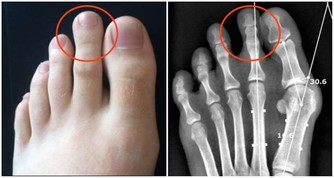

這是一種影響所有年齡段人群的長期病症。最常見的類型是骨關節炎,由關節內光滑的軟骨逐漸磨損引起的。其症狀包括關節疼痛、壓痛、僵硬,並且在受影響的關節上皮膚會出現紅腫。

如果你超重,減掉幾斤可以幫助你控制關節炎的疼痛。因為如果體重太重,會給臀部和膝蓋的關節帶來額外的壓力,這可能會導致更嚴重的疼痛。